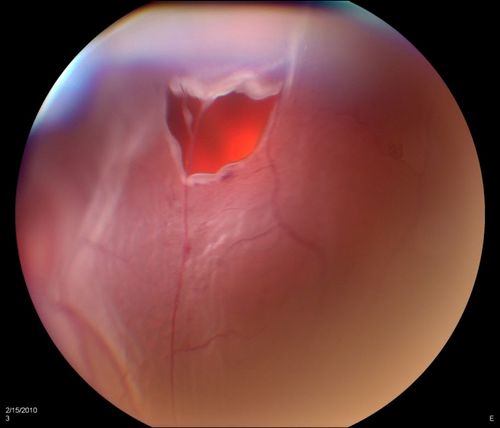

Horseshoe Retinal Tear with bridging blood vessel

Retinal Detachment